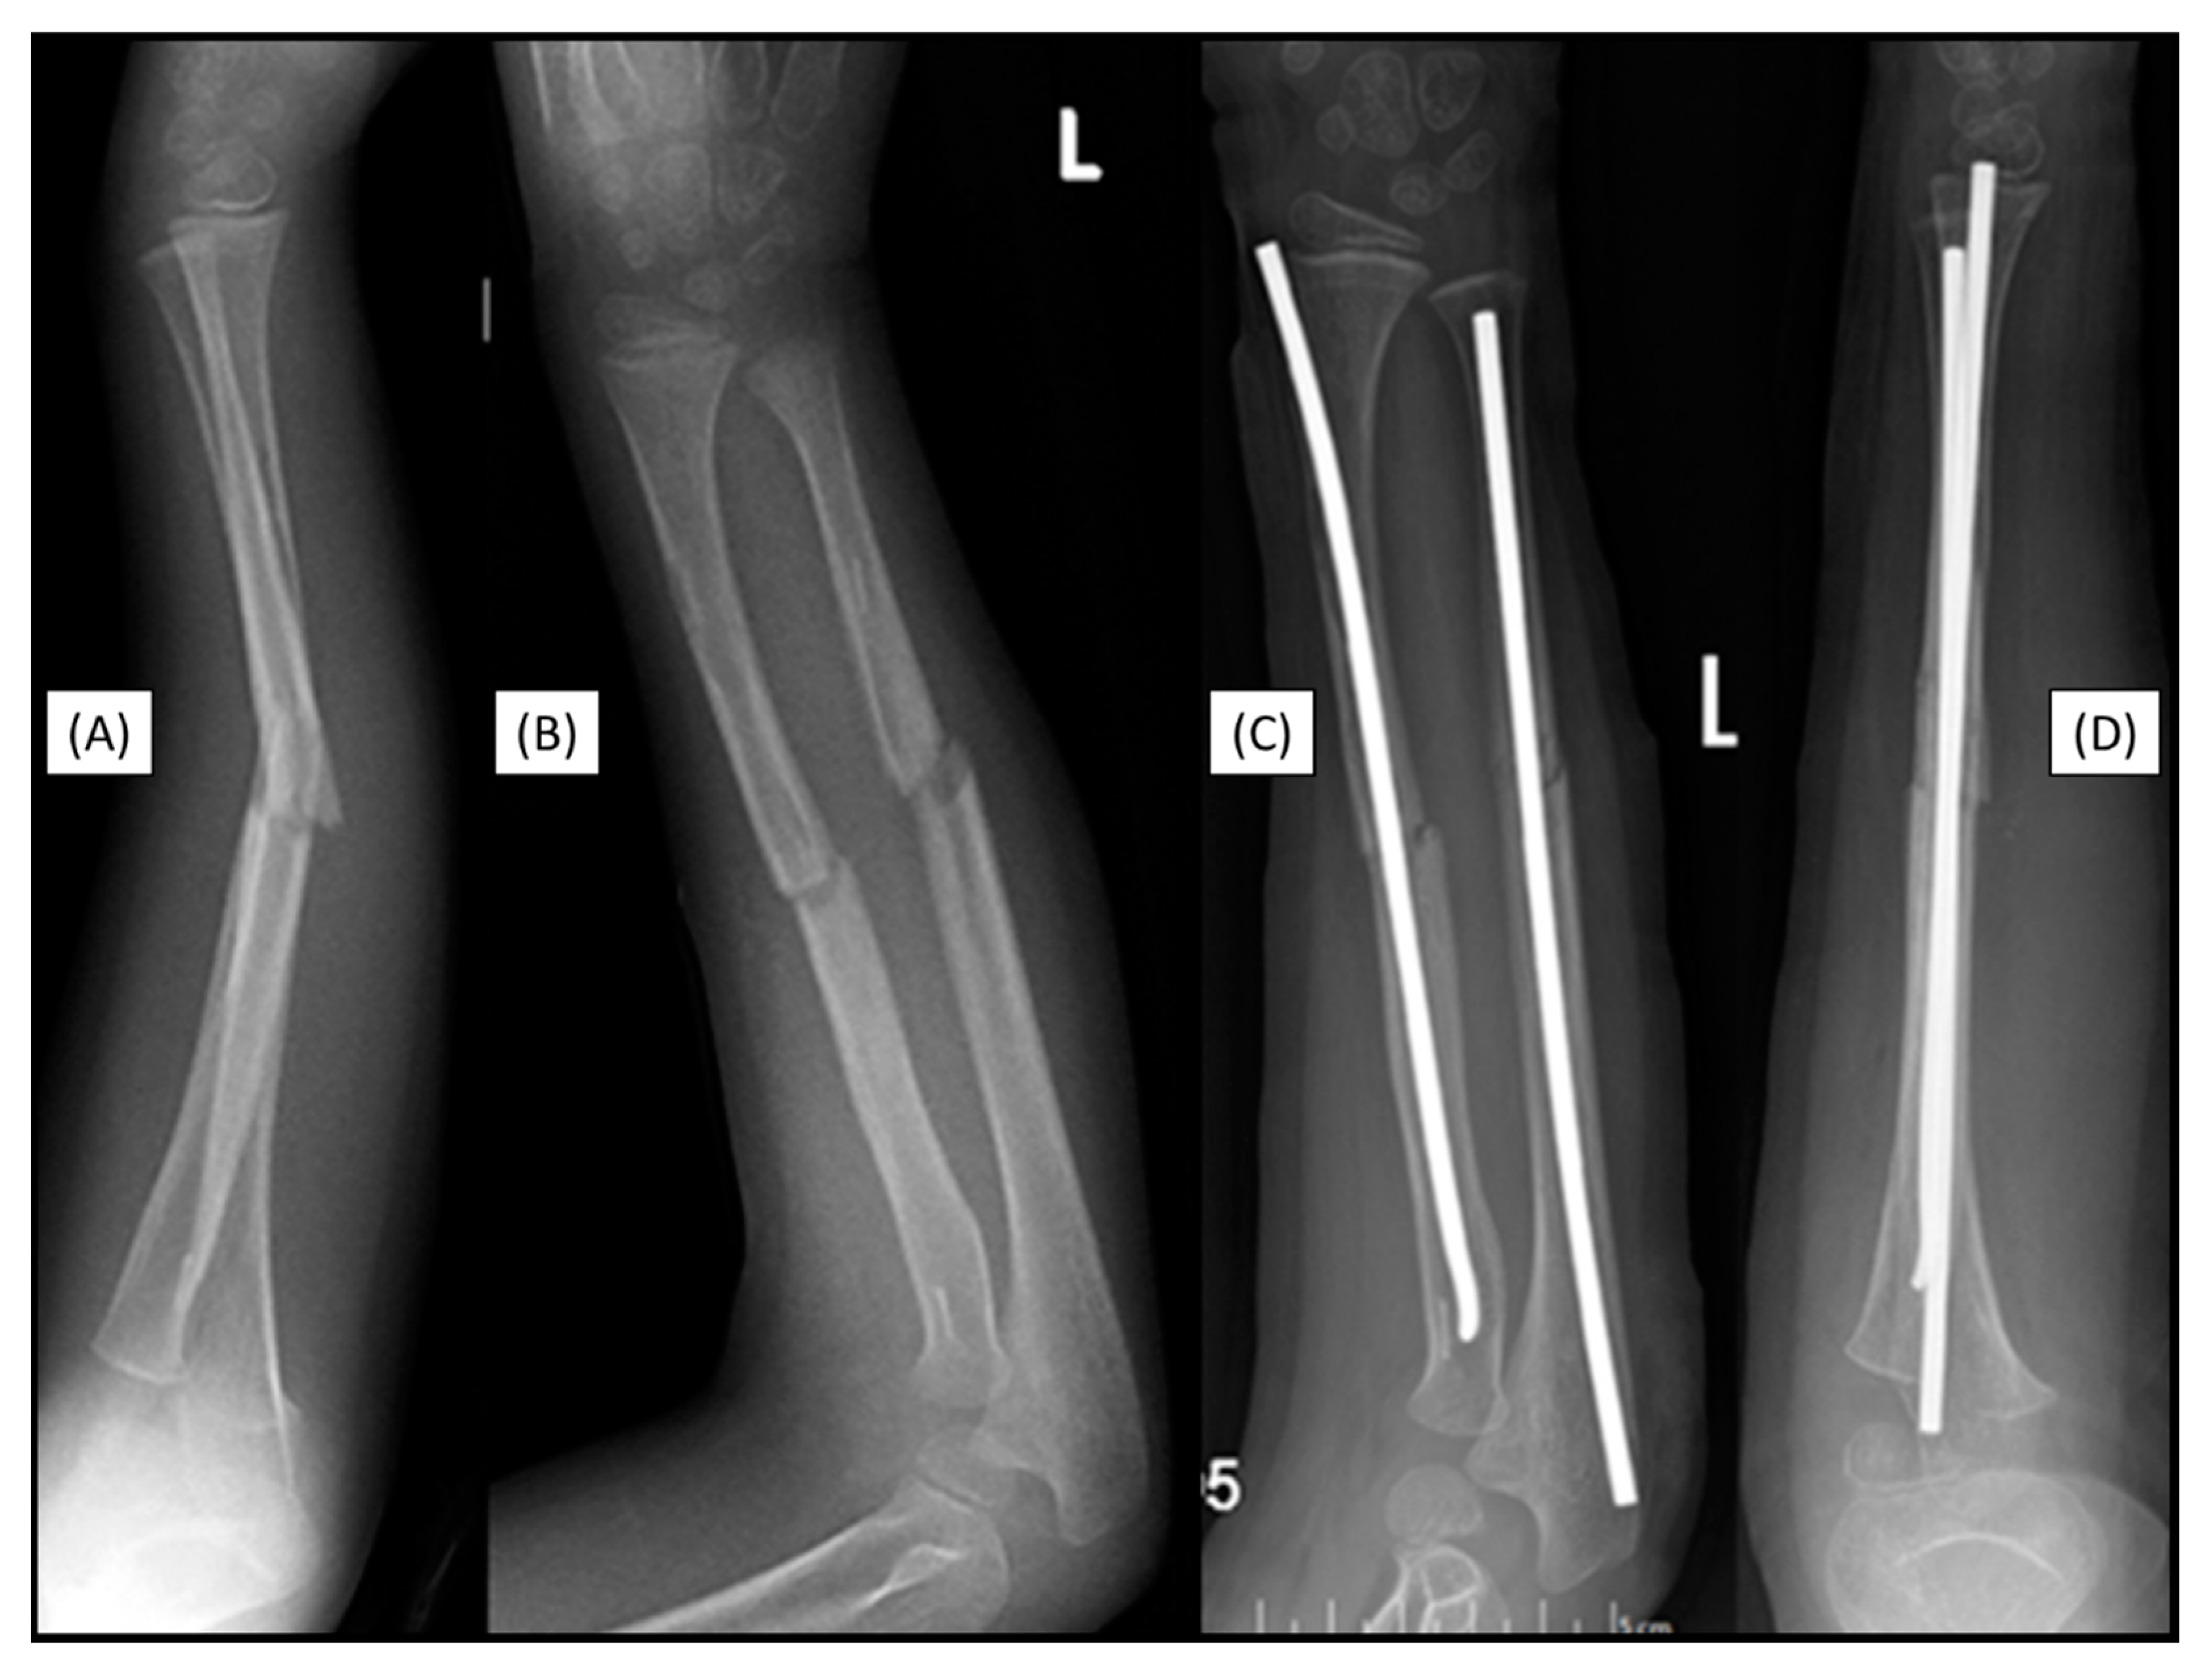

3.7. Case 7: Recurrant Fracture

The forearm fracture (22-D/2.1.) of a 7-year-old boy was fixed with a primary absorbable intramedullary implant. Two years after the closed reduction and fixation of a left forearm diaphysis fracture with a BIN implant, a repeated not implant related forearm diaphysis fracture occurred the injury was caused by a fall from a horse. (Figure 7(A-B). After closed reduction, the forearm bones were stabilized with titanium ESINs. During the surgery, no resistance was encountered in the IM space, and the medullary cavity was free, allowing for smooth insertion of the titanium implant without any difficulties (Figure 7(C-D).

Figure 7. Markers are visible in both bones two years after the primary treatment with BINs (lateral (A), AP (B)). Postoperative X-rays show the perfect alignment of the forearm, stabilized with ESINs (AP (C), lateral (D)).